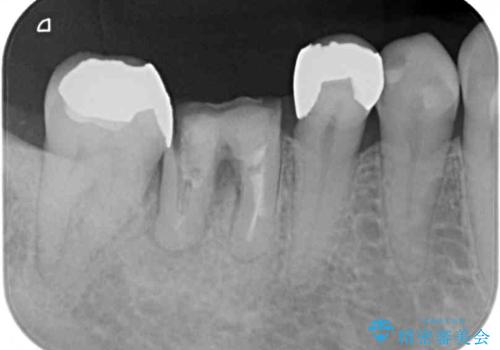

- 他院で、抜歯してインプラント補綴するしかないとのことで来院された患者様です。

診査したところ、抜歯と診断された歯は、他院での診断通り抜歯が必要でした。

ただし、インプラント以外にブリッジでの補綴治療も可能であったので、抜歯後に治癒を待って、フルジルコニアブリッジにて補綴することとしました。